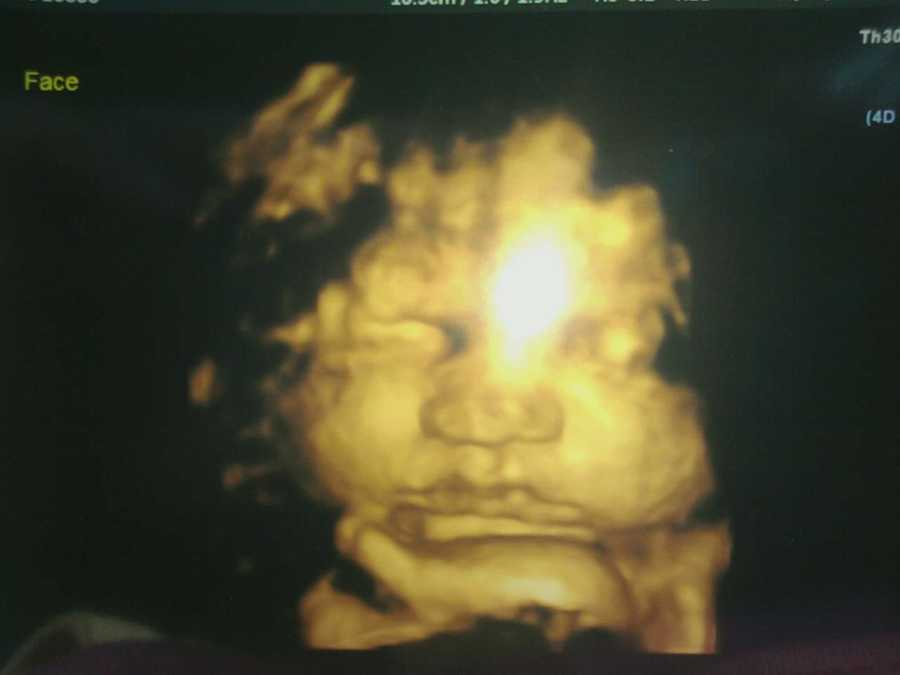

She was 22 and pregnant with her first child, a baby boy. She and her partner were thrilled to be expecting, and at first, everything seemed normal. At their first sonogram, she heard the baby’s heartbeat and cried tears of joy. It finally felt real. But a few weeks later, everything changed. At the next appointment, the doctor told them the baby “carries a marker that points to Down Syndrome,” he said, a key bone (the nasal bone) was missing. Then later, during another ultrasound, she noticed something was wrong: the baby’s long bones looked bent, almost like they were broken. Her mom saw it too. They looked at each other and knew this wasn’t okay.

From that point, the doctors started using words she barely understood: dwarfism. Brittle bone disease. Genetic disorders like Trisomy 13, 14, or 18. She was terrified, she called her husband at work and told him something was wrong with the baby. They were sent for more ultrasounds, specialist visits, and tests. They learned they were having a boy. They examined her. I was 4 feet 11 and said she might have a mild form of dwarfism. If so, maybe the baby could also have it. But still, with so many questions at about 23 weeks, they had an amino test. She’ll never forget how scary it was to see a needle going close to her belly, begging silently for the baby not to move.

Her world was shattered. Despite all the fear and confusion, they tried to stay hopeful. They had a baby shower. They bought tiny clothes, dreamed of holding him, planning his life. She tried to believe that maybe, just maybe, things could be okay at 37½ weeks; she went in for another ultrasound. She was so afraid. But when the technician scanned the baby’s legs, she froze. The bones looked normal. Straight. The crooked, broken-looking bones from earlier had vanished. Her grandma, who was with her, gasped. She couldn’t believe it. The doctor was cautious: he warned us to “be prepared for the worst.” But she turned to him inside, “Don’t ruin this,” she thought.